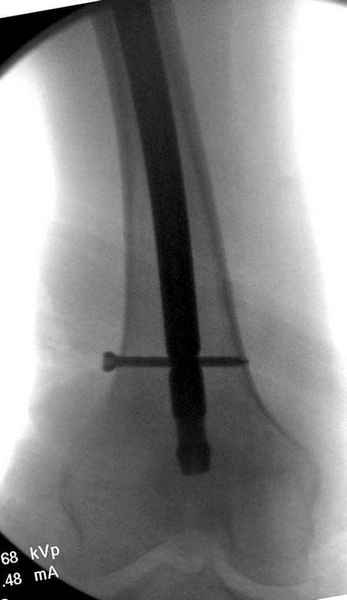

На второй день после выписки упал дома. Снимки приложены. Коллеги рекомендуют удаление шурупа и вытяжение. Что делать?

Правильно, ситуация изменилась, как говорят у нас теперь "different animal", надо решать проблему подвертельного перелома. При наличии различных вариантов фиксаторов, включая Страйкер Гамма 3, мы выбрали DePuy Antegrade Trachanteric Nail из-за многовариантности проксимальной фиксации и двойного изгиба. Вводится через вертел под 8 градусным углом, и есть достаточный передний диафизарный изгиб, предупреждающий пенетрацию дистального переднего кортекса.

Кто знает что дальше, мысленно готовы к проксимальной артропластике.